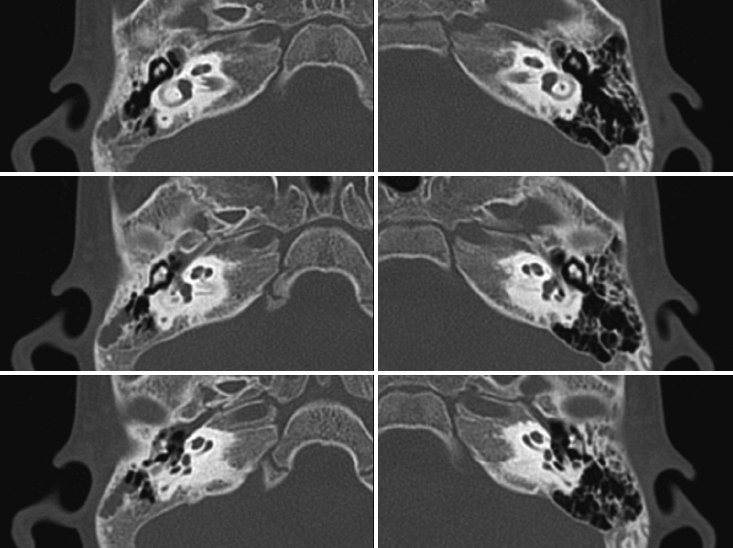

출생 후 시행한 신생아 청각선별검사 상 양측 재검 소견 보여, 생후 2개월경 시행한 청성뇌간반응검사 상 양측 모두 90 dB에 반응없음 소견 보인 6개월 된 환아가 내원하였다. 청력 이외에 다른 기형이나 발달 상의 문제를 보이지는 않았다. 3개월 이상 보청기를 양측에 사용하였으나 외부소리에 대해 반응을 전혀 보이지 않았고, 생후 11개월에 시행한 temporal bone computed tomography (TBCT) 소견은 아래와 같았다. 11개월에 시행한 청성뇌간반응검사 및 청성지속반응 검사에서 모두 반응없음 소견을 보였다.

해 설 양측 인공와우 수술의 적응증이 되는 환아로 폐렴구균 예방접종을 시행해야 한다. 2세 미만에서는 7 또는 13가의 폐렴구균 결합백신을 사용할 수 있으며, 2세 이상에서는 폐렴구균 피막다당류백신(Pneumococcal polysaccharide vaccine, PPSV23)을 시행한다. temporal bone computed tomography(TBCT) 상 양측의 bony cochlear nerve canal(BCNC) stenosis가 관찰된다. MR을 시행하여 cochlear nerve의 존재 유무를 확인해볼 수 있다. BCNC stenosis의 경우 그렇지 않은 경우에 비해 인공와우 수술후의 예후가 좋지 않음이 보고되고 있다. 청성뇌간 이식술의 고려대상이 될 수는 있으나, 아직 청성뇌간이식술의 결과가 예측하기 어렵고, BCNC stenosis 환자에서 인공와우수술 후에도 비교적 좋은 결과를 보이는 경우도 있기 때문에 청성뇌간이식술을 우선적으로 고려하기는 어렵다.